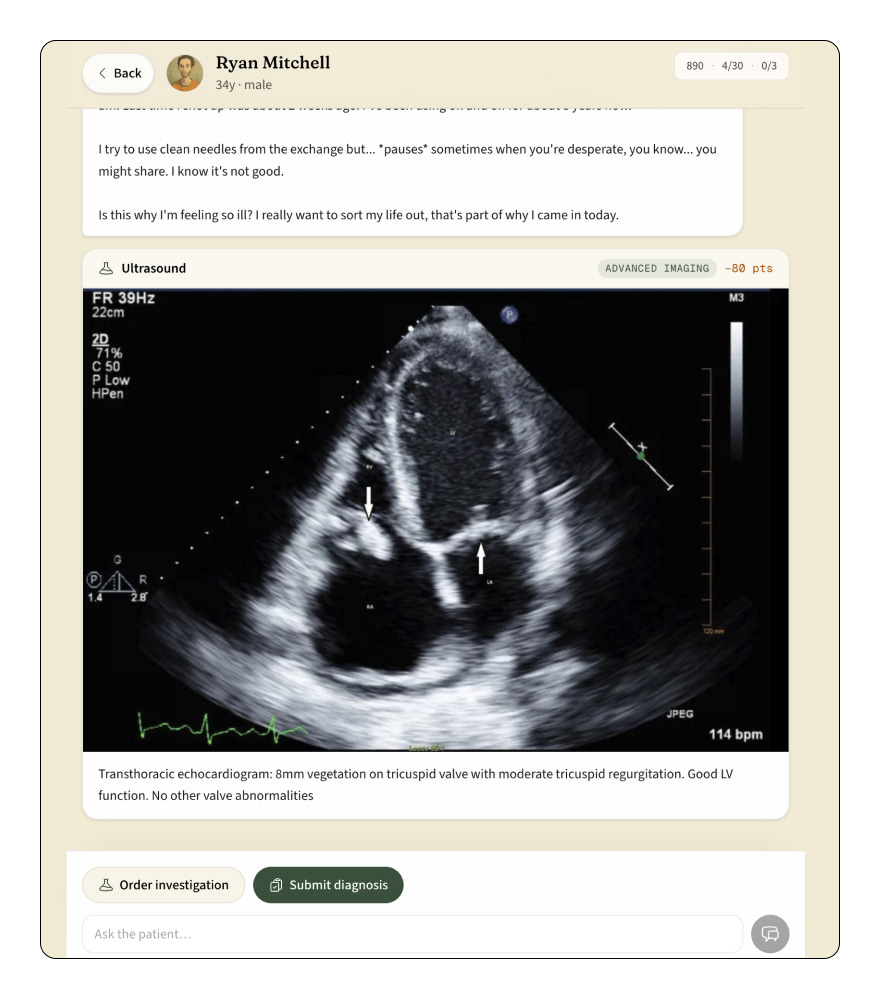

You start by talking to the patient. Ask questions in natural language. The AI responds in character, sharing symptoms, history, and concerns the way a real person would... gradually, sometimes imprecisely, always grounded in a pre-authored clinical case that ensures medical accuracy.

When you think you have enough from the conversation, you can order investigations. Physical exams. Blood tests. ECGs. Imaging. Biopsies. Each investigation has a point cost, because in the real world, ordering every test under the sun isn’t good medicine. It’s lazy medicine.

Then you submit your diagnosis. You get three attempts to pick the correct one from a curated database of over 1,100 conditions across 20 medical specialties.

Your score rewards efficiency: fewer messages, fewer investigations, fewer diagnosis attempts. The best doctors aren’t the ones who order everything. They’re the ones who ask the right questions.